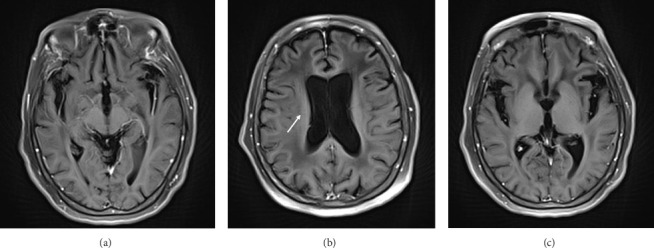

Introduction: Gliomatosis cerebri (GC) is a diffuse neoplastic process, whose presentation is extremely rare and lacks a characteristic clinical pattern. The objective of this case is to describe the clinical aspects of a patient with GC, in whom symptoms of parkinsonism and neurocognitive issues predominate. Case Report: A 78-year-old patient with no significant medical history was referred to the neurology consultation due to balance disturbances accompanied by head tremor. Symptoms of parkinsonism progressively worsened, adding cognitive and neuropsychiatric disorders. Cranial magnetic resonance imaging (MRI) showed diffuse and generalized white matter hyperintensity. Under the suspicion of GC, a frontal lobe biopsy was performed, with a pathology report of diffuse astrocytoma, thus confirming the diagnosis of GC. Conclusion: GC is a disease that presents with nonspecific clinical manifestations, making a clinical diagnosis challenging. It should be suspected in cases of parkinsonism accompanied by other focal neurological disorders. This leads to delayed diagnosis and consequently low incidence. The importance of MRI as a diagnostic aid is highlighted, with biopsy being necessary to confirm the diagnosis.

脑胶质瘤病(Gliomatosis cerebri, GC)是一种弥漫性肿瘤,其临床表现极为罕见,缺乏特征性的临床模式。本病例的目的是描述GC患者的临床方面,其中帕金森症状和神经认知问题占主导地位。病例报告:一名78岁无明显病史的患者,因平衡障碍伴头部震颤而就诊神经内科。帕金森氏症的症状逐渐恶化,增加了认知和神经精神障碍。颅脑磁共振成像显示弥漫性广泛性白质高信号。在怀疑为胃癌的情况下,行额叶活检,病理报告为弥漫性星形细胞瘤,确诊为胃癌。结论:胃癌是一种临床表现非特异性的疾病,临床诊断具有挑战性。在帕金森病合并其他局灶性神经系统疾病的病例中应怀疑。这导致诊断延迟,从而降低发病率。MRI作为诊断辅助的重要性被强调,活检是必要的,以确认诊断。